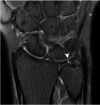

Q. ¿PRINCIPALES HALLAZGOS DE ESTAS IMÁGENES Y A QUE GRADO INESTABILIDAD ROTATORIA POSTEROLATERAL (PLRI) CORRESPONDE ?

Inestabilidad rotatoria posterolateral, grado 1. Resonancia magnética ponderada por PD del FS coronal que muestra una avulsión de la colateral del ligamento cubital lateral proximal y retracción del fragmento óseo (flechas blancas). El edema de la médula ósea se observa en el capitelo (puntas de flecha blancas) y la cabeza radial (asteriscos blancos).